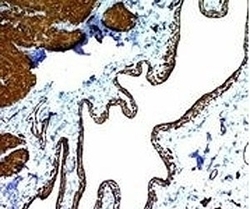

- Main image

- Experimental details

- Formalin-fixed, paraffin-embedded human colon carcinoma stained with alpha Smooth Muscle Actin antibody (ACTA2/791). This image was taken for the unmodified form of this product. Other forms have not been tested.

- Main image

- Experimental details

- Formalin-fixed, paraffin-embedded human colon carcinoma stained with alpha Smooth Muscle Actin antibody (ACTA2/791). This image was taken for the unmodified form of this product. Other forms have not been tested.